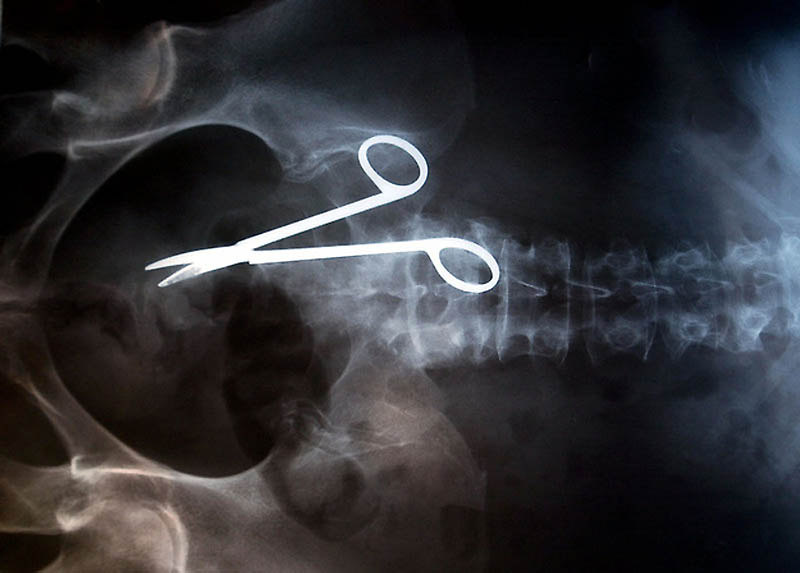

Хирургические ножницы, случайно забытые в теле пациентки после операции. Ножницы были обнаружены лишь через 18 месяцев после операции, т.к. женщина жаловалась на постоянную боль в кишечнике